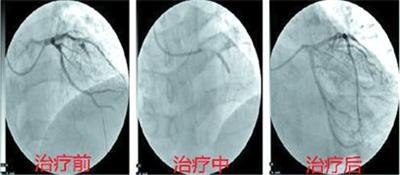

手术成功帮助患者打通闭塞血管。

尹作民马上向青岛市中心医疗集团医务部汇报,多伦县人民医院将会诊申请传送到青岛市中心医疗集团。向患者家属交待病情后,多伦县人民医院导管室开通,一场与时间赛跑的生命救援就此展开。9时25分,患者到达导管室;9时35分穿刺成功;9时50分球囊扩张完成,门球时间75分钟;最后植入支架一枚,患者转危为安。至此,所有人都松了一口气。